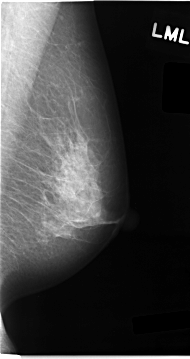

C_0061_1.LEFT_MLO

LEFT_MLO LINES 4664 PIXELS_PER_LINE 2464 BITS_PER_PIXEL 12 RESOLUTION 50 NON_OVERLAY